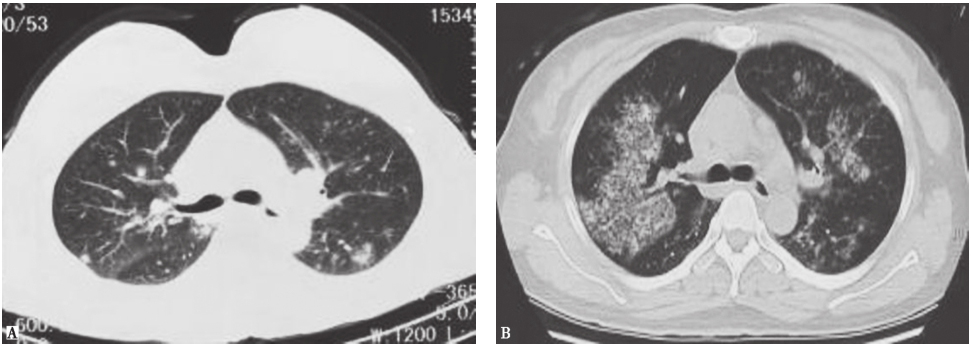

图6高分化腺癌胸部CT表现

男性患者,37岁,因咳嗽9个月入院,病理检查证实为高分化腺癌。胸部CT表现为两肺野多发斑点状、斑片状结节影及模糊环状低密度影,病灶形态欠光整